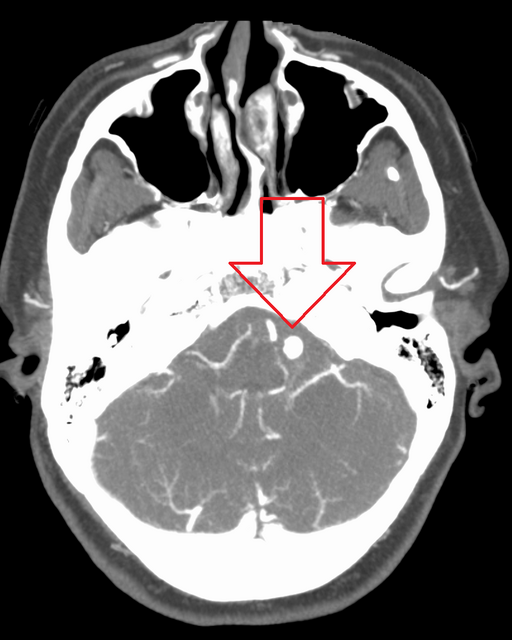

Kim Kardashian's latest health revelation on The Kardashians has triggered widespread concern after a brain scan reportedly uncovered 'low brain activity' in her frontal lobes and a small, previously unnoticed brain aneurysm.

The episode, filmed in late 2025, featured psychiatrist Dr Daniel Amen, who pointed out 'holes' in Kardashian's scan—an interpretation that drew immediate public attention.

During the episode, the celebrity psychiatrist Dr Daniel Amen pointed out what he described as 'holes' in the scan, signalling reduced activity, particularly in the frontal lobes. He cautioned that this could make stress management much more complicated at a time when Kardashian is juggling high-pressure commitments: studying for the California bar exam, public appearances, and high-stakes personal matters.